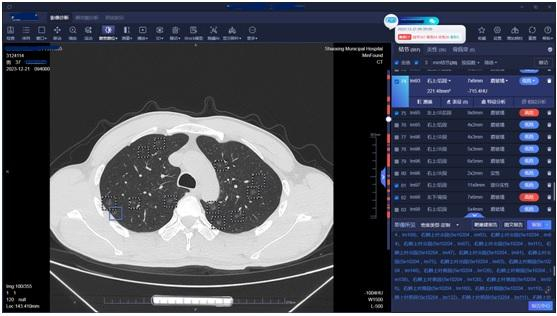

胡军告诉医生,他3年前就查出多发性肺部结节,这几天出现咳痰、胸闷等症状。肺结节人工智能软件提示,其双肺竟有557个磨玻璃结节,其中高危的有26个。

医生说,综合临床各项检查数据与资料,诊断最终倾向早期肺恶性肿瘤(早期肺腺癌可能)。患者还很年轻,肺部磨玻璃结节又太多,每一个都像地雷一样埋在肺里,要是突然暴发,连手术机会都没有。

“我发起了肺结节多学科联合会诊,胸外科、呼吸与危重科、影像科的专家都来了。”医生说,通过激烈讨论、反复论证,大家最终提出了适合胡军的个性化治疗方案:在放射介入科完成选定的高危靶结节穿刺定位,然后在胸外科行腔镜下结节微创切除活检,获取病理结果和肿瘤基因检测结果。结果显示,胡军患有肺腺癌。